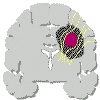

Un glioma può essere quindi distinto in tre tipi (Daumas-Duport): |

Tipo

I: lesione circoscritta |

II: lesione compatta ed area di tessuto cerebrale infiltrato |

III: lesione diffusa con parenchima infiltrato |